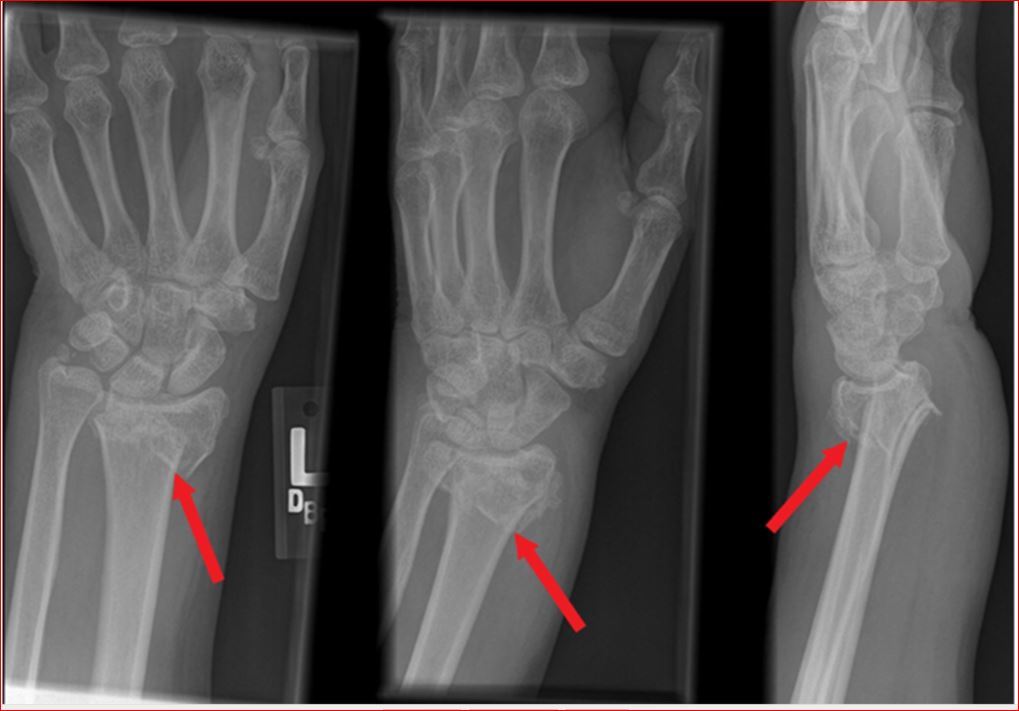

Shows distal radius fracture with shortening and dorsal displacment.

This injury is known as Colles’ fracture.

Ulnar styloid fracture, scaphoid fracture and acute carpal tunnel syndrome

Management of Distal Colles fracture

Most can be managed with conservative measures such as sugar tong splinting, with or without closed reduction.

More severe injuries, especially those with significant displacement or angulation >15-20 degrees may require urgent orthopedic consultation for possible surgical intervention